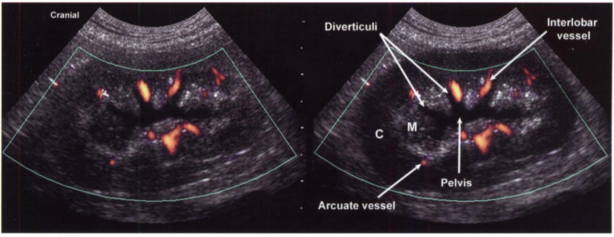

Для адекватных замеров почку необходимо чётко вывести в поперечной проекции чтобы визуализировался весь почечный синус. Лоханку измеряем от почечного гребня до входа в мочеточник. (рис 2). Любая анэхогенная структура в почке всегда взывает сомнения, тут на помощь нам приходит ЦДК или энергетический доплер. С его помощью мы можем отличить сосуды от патологической полости, это как раз очень важно, т.к. вдоль рецессусов проходят междольковые сосуды и их часто путают с расширение рецессусов и неправильно диагностируют гидронефроз.(рис 1).

Рис 1. Ультразвуковое и схематическое изображения левой почки в сагиттальной плоскости сканирования. Почечная лоханка расширена, также как и дивертикулы, которые можно отличить от междольковых сосудов (Interlobal vessel) только с помощью энергетического доплера.